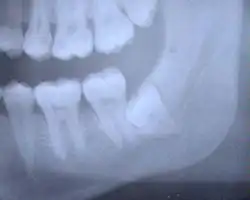

Die folgenden Röntgenbilder sind Ausschnitte aus Orthopantomogrammen (OPG):

Weisheitszahn 38; retiniert und verlagert; mesiale Kippung um fast 90°